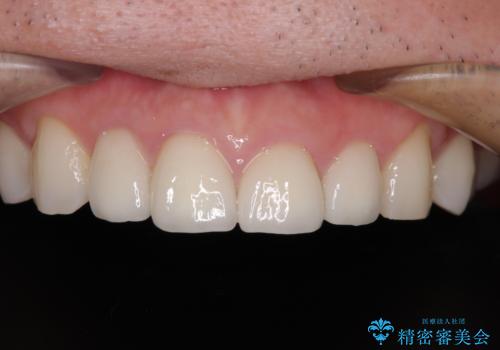

根管治療のやり直しは希望されなかったため、土台のやり替えと、より自然なオールセラミッククラウンへのやり替えを行いました。

自然できれなオールセラミッククラウンになり、とても満足されました。